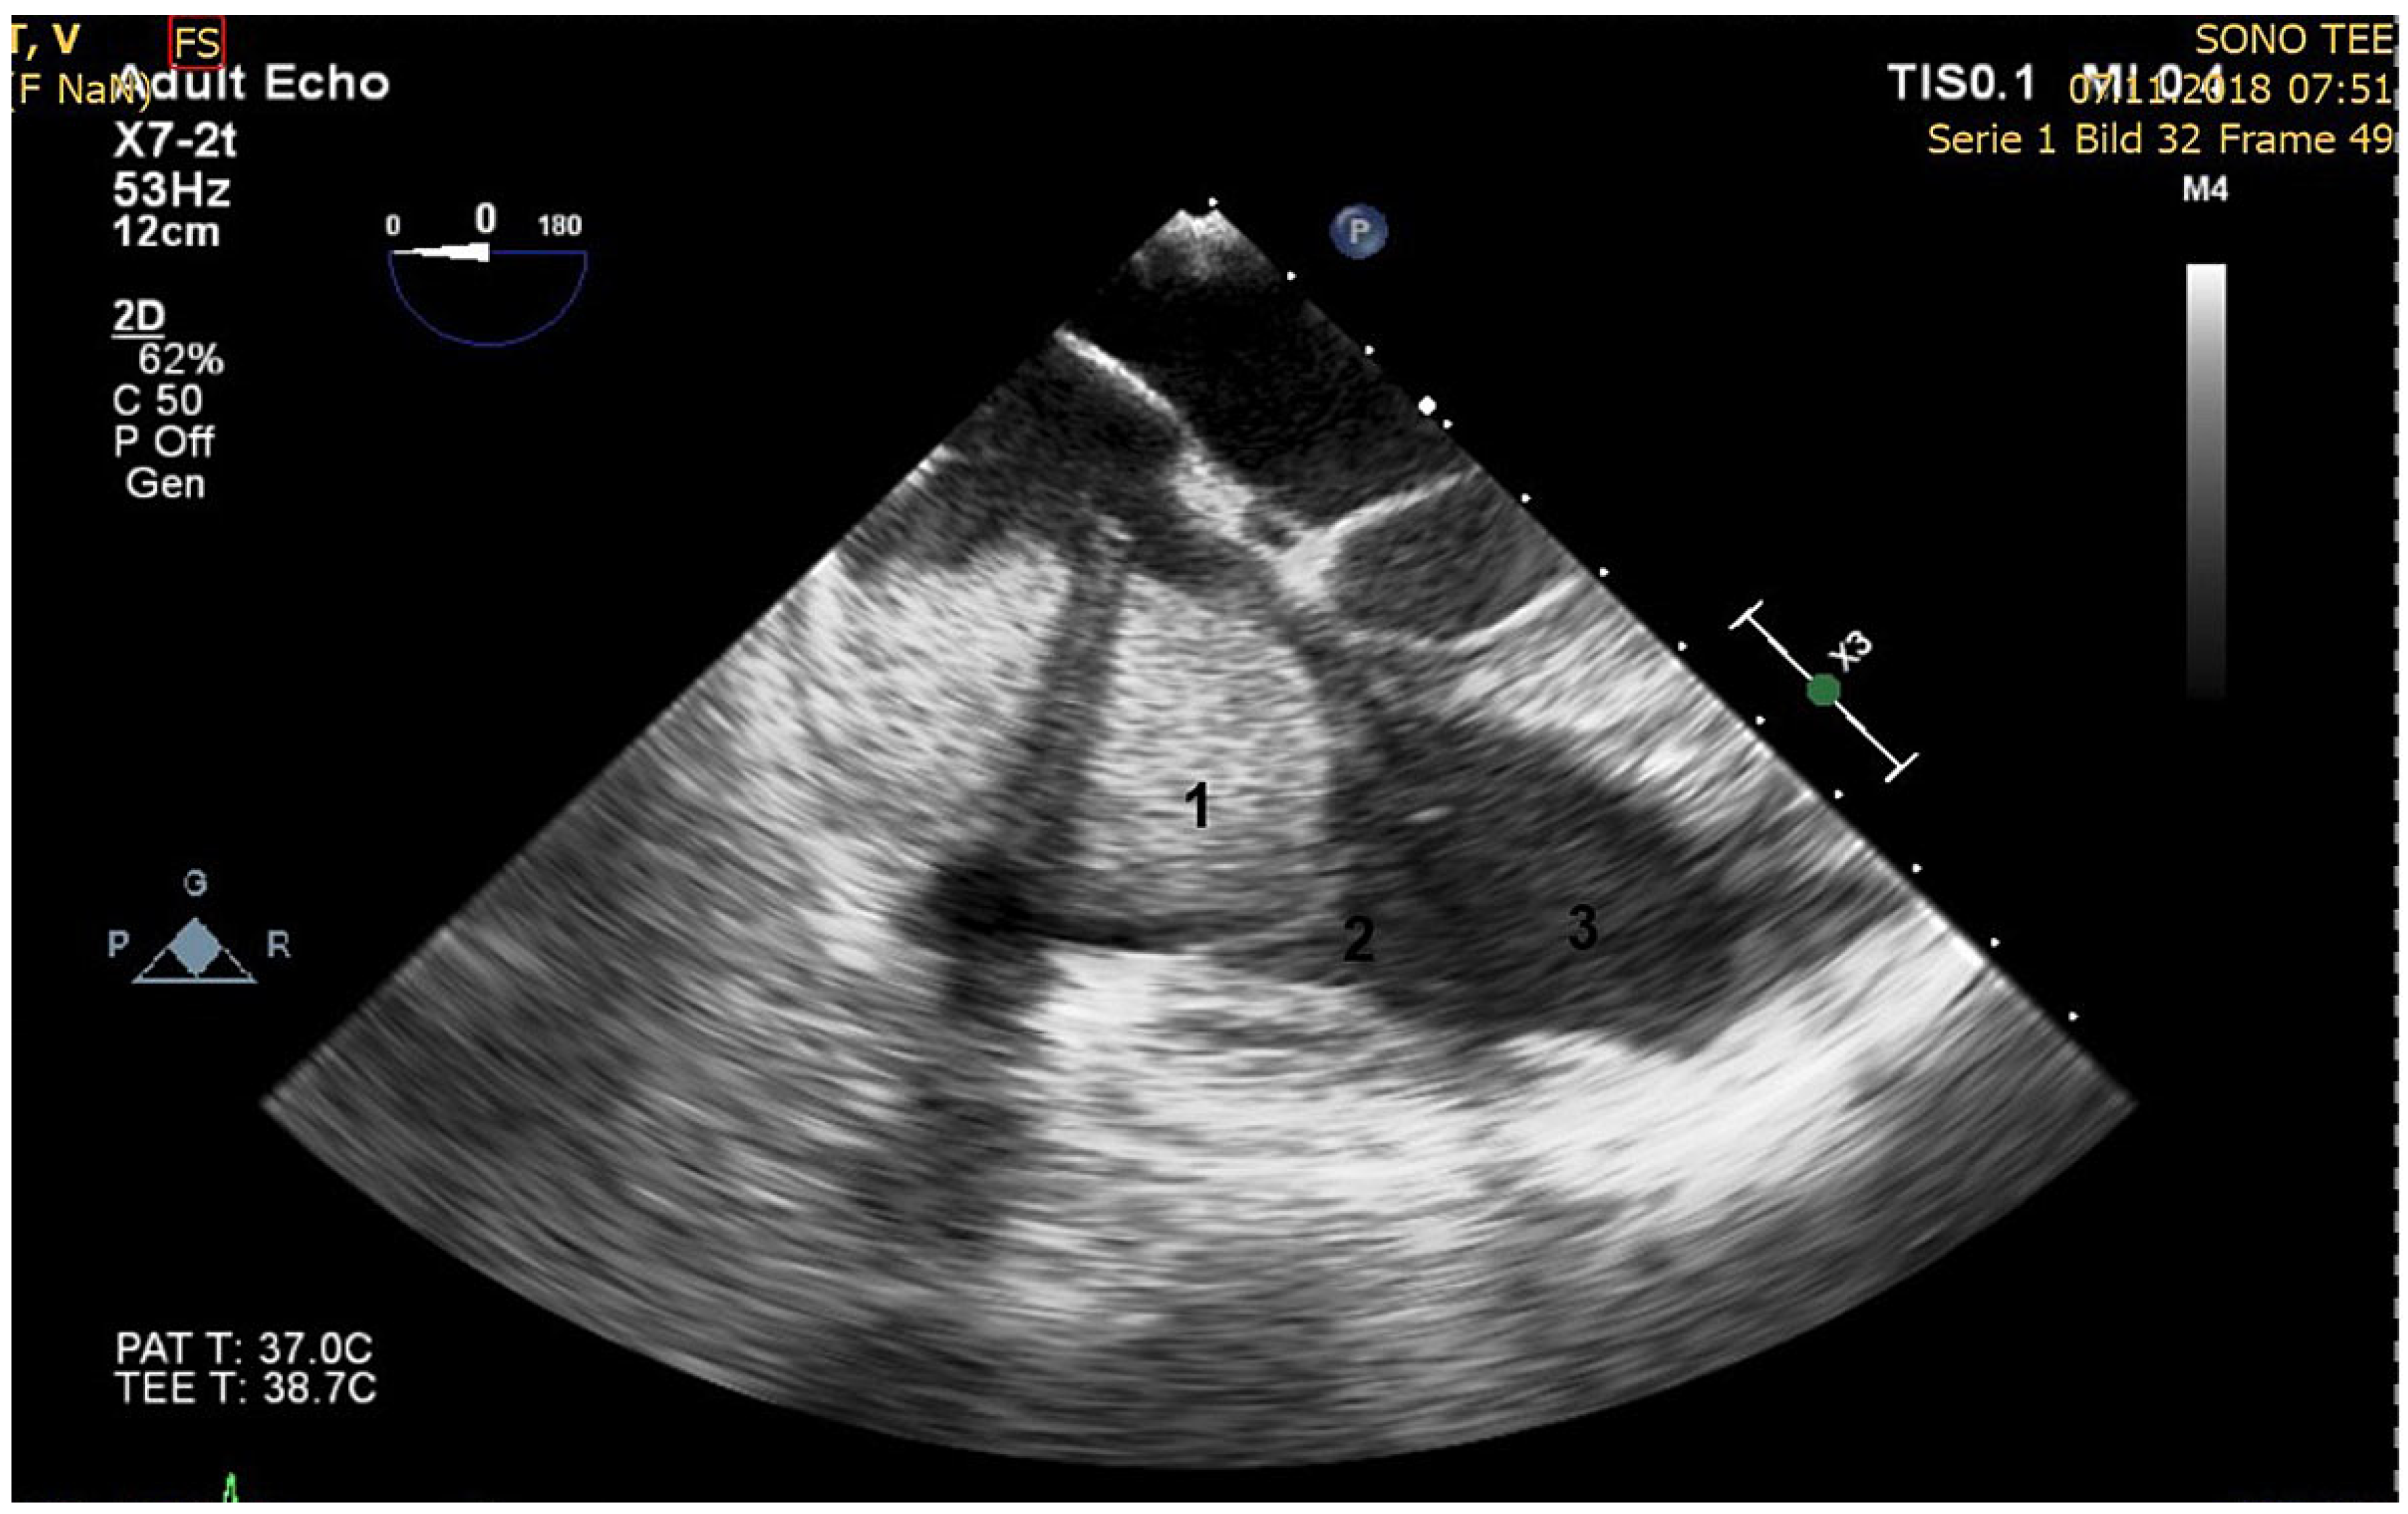

Major Right Atrial Thrombus Related to Central Venous Catheter Positioning

Case description